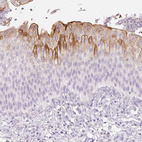

Immunohistochemistry analysis in human urinary bladder and liver tissues using HPA061106 antibody. Corresponding UPK2 RNA-seq data are presented for the same tissues.